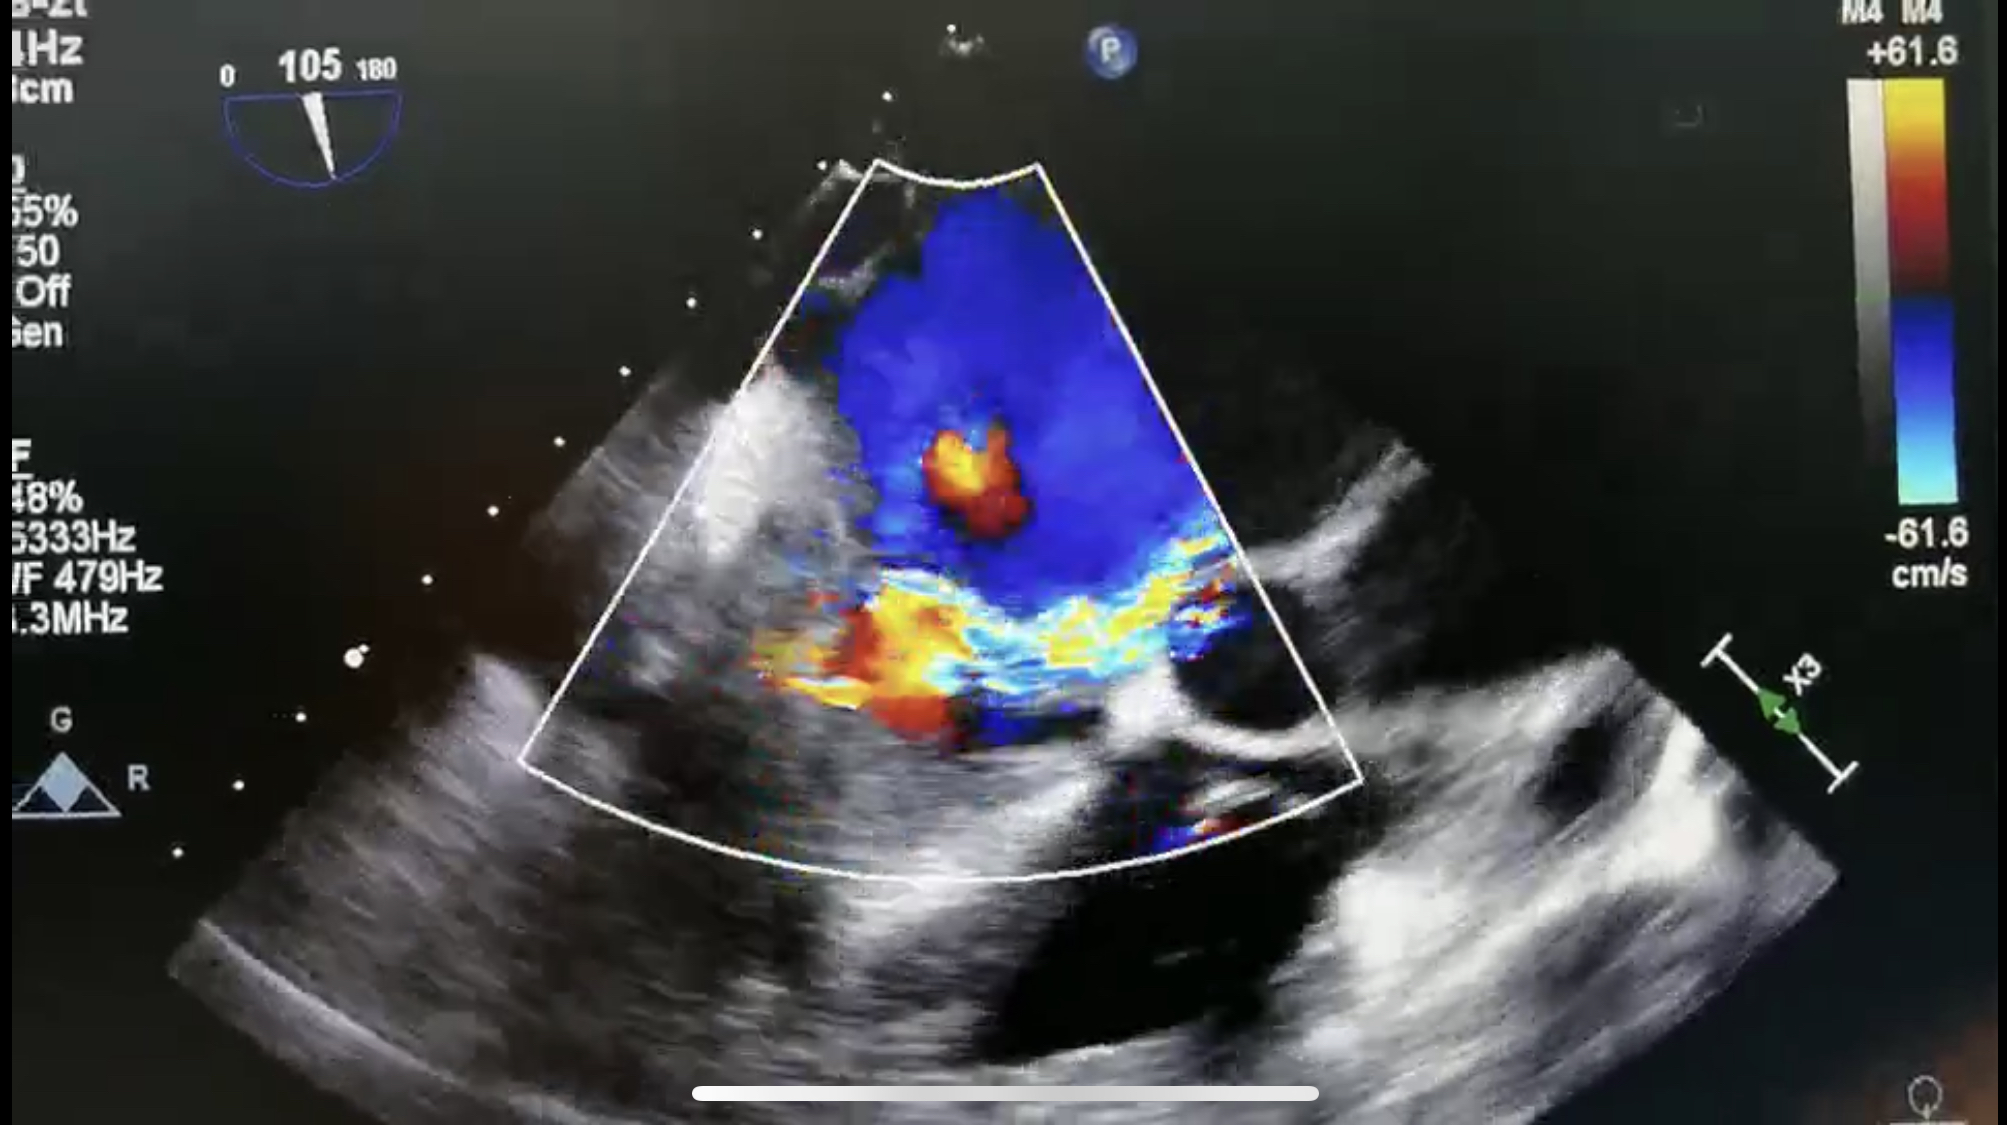

患者术前及术后彩超

释放二尖瓣夹后,超声显示返流程度由大量转为少量返流,患者各项生理指标正常,手术顺利完成,耗时约两小时。